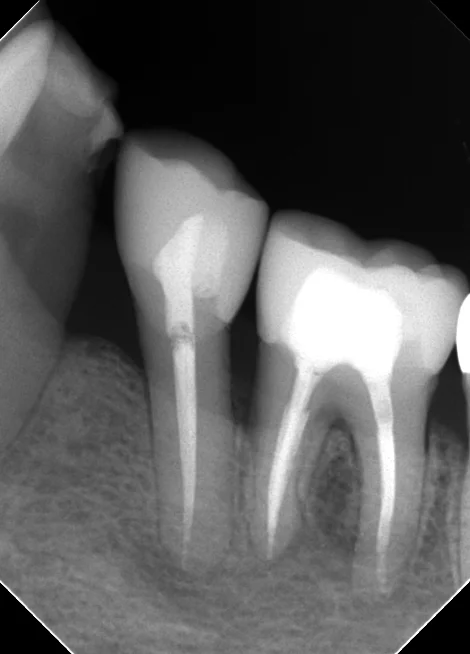

そしてその後、1年経過時点でメンテナンスで来院された際に再度レントゲンを撮らせて頂きました。

ほとんど完全に黒い部分が消えてくれているのが分かるかと思います。

治療終了後はセラミックを希望されたので、通法に則って形作り・型取りを行い、Setしました。

レントゲンを見る限りだと適合は非常に良いですね。